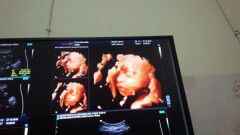

Ibu hamil

laki2 atau perempuan ?

Dari wajah prenatal alias janinnya cowok banget ya bun ? Abatinya (ayahnya) banget mukanya :) In syaa Allah kata dokter anak kami perempuan ^^ Mohon do'anya ya bunda2 semoga anak kami sehat2 selalu. Sudah 1 minggu saya pendarahan bun :"